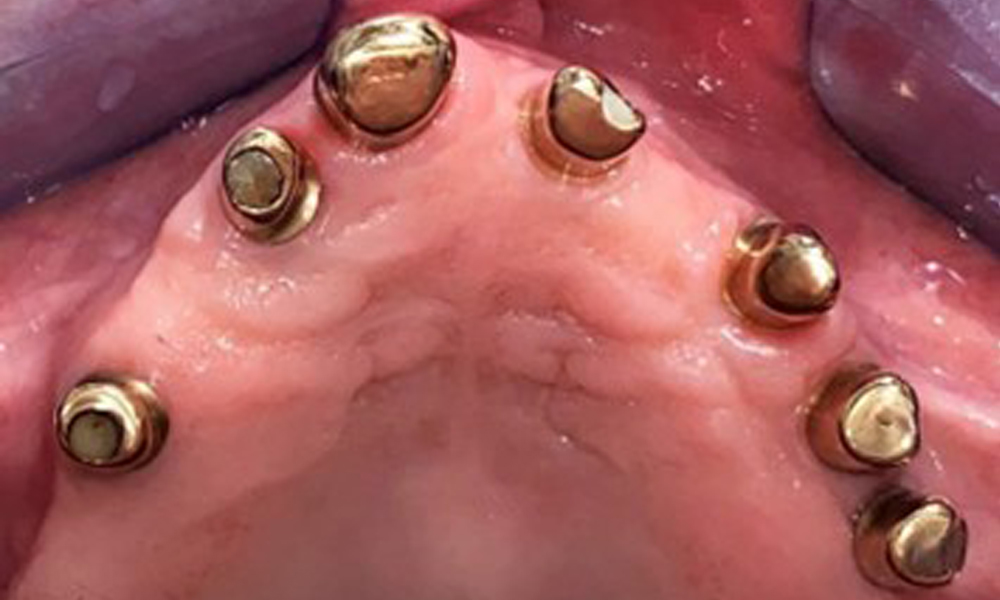

Occlusal view: Maxilla with tooth and implant-supported telescopic prostheses.

Fig. 2: Occlusal view: Maxilla with tooth and implant-supported telescopic prostheses

The dental findings are as follows: Combined removable implant and tooth-supported telescopic prostheses on implants 15, 13, 21, 23, 24, 25 and tooth 11 (Fig. 1, Fig. 2, Fig. 3). The patient was fitted with a fixed mandibular denture. Adequate bridges were present over 37 to 34 and 45 to 47 (Fig. 4), the crown margins were intact and there were no active caries. A composite filling with a marginal gap was present on tooth 43. There was mandibular gingival recession, exposing 1 to 3 mm of root surface. This also applies to 11.